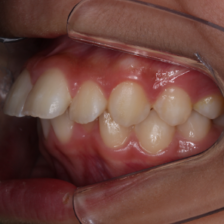

だらだらと長期間治療をするのではなく、ベストなタイミングを見計らい、一気に治療を終わらせます。

歯科医師としてはもちろんのこと、同じ子を持つ親として、保護者様の視点に立った治療を心掛けています。